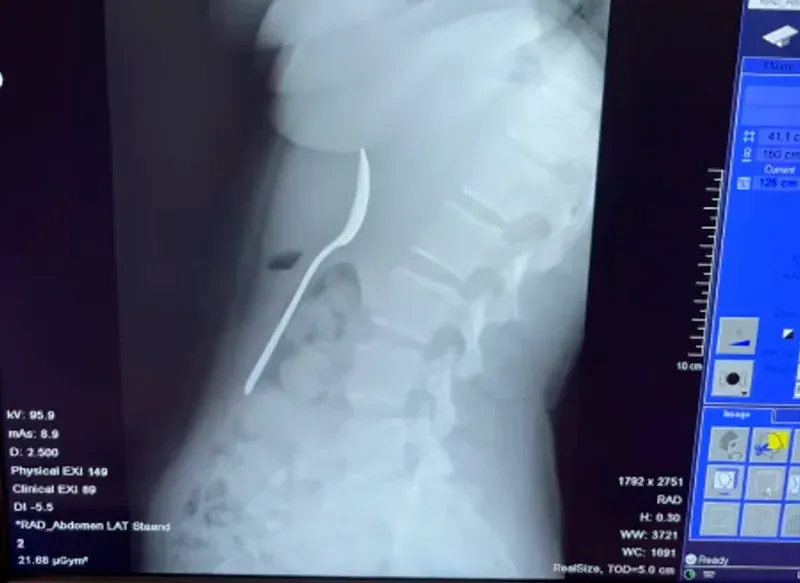

หลังเกิดเหตุ เธอไม่กล้าบอกแฟนหนุ่มในทันทีเพราะความอับอาย จนกระทั่งหลังมื้อค่ำ อาการเริ่มแย่ลงเรื่อยๆ เธอจึงถูกส่งตัวไปยังโรงพยาบาล แพทย์ถึงกับตะลึงเมื่อเห็นภาพเอกซเรย์ เพราะช้อนมีขนาดใหญ่เกินกว่าจะขับถ่ายออกมาเองตามธรรมชาติได้ เธอต้องรอคิวทำส่องกล้องนานถึง 2 วัน ซึ่งในช่วงเวลานั้นเธอยังรู้สึกได้ว่าช้อนเคลื่อนที่ไปมาอยู่แถวซี่โครง สร้างความเจ็บปวดและทรมานเป็นอย่างมาก

โชคดีที่ทีมแพทย์สามารถนำช้อนออกมาได้สำเร็จผ่านการวางยาสลบเฉพาะจุด แม้กระบวนการจะยากลำบากเพราะขนาดของช้อนที่ต้องปรับองศาอย่างระมัดระวังจนทำให้มีเลือดออกในกระเพาะอาหารเล็กน้อย และมีอาการเจ็บคอตามมาอยู่พักใหญ่ แต่ในที่สุดเธอก็หายเป็นปกติโดยไม่มีความเสียหายถาวรต่อร่างกาย